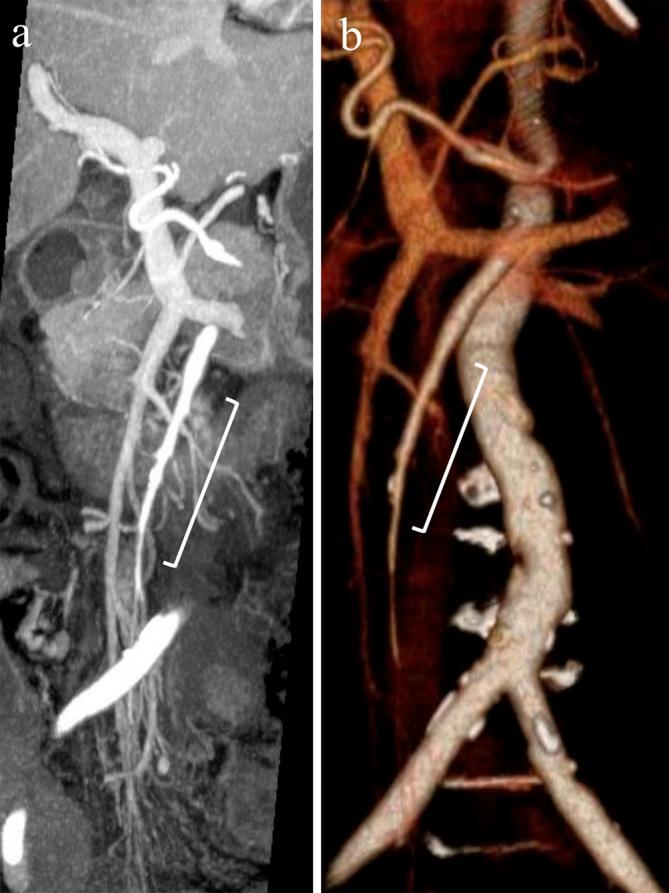

Acute mesenteric ischemia is a life-threatening condition. A comprehensive approach involving a multidisciplinary team to review patient background, clinical history, physical examination, laboratory data, and imaging examination for respective diagnosis of superior mesenteric arterial occlusion, nonocclusive mesenteric ischemia, and superior mesenteric venous occlusion is essential. The most important imaging modality is computed tomography, which is used for diagnosis and for directing therapeutic strategy (e.g., endovascular revascularization, surgical bowel resection, or conservative management). Computed tomography image findings can support triaging of irreversible transmural bowel necrosis compared with reversible ischemic change with reperfusion. In this review article, the computed tomography imaging findings specifically associated with the pathophysiology of superior mesenteric arterial occlusion, nonocclusive mesenteric ischemia, and superior mesenteric venous occlusion are reviewed.

急性肠系膜缺血是一种危及生命的疾病。采用多学科团队的综合方法来审查患者背景、临床病史、体格检查、实验室数据以及影像学检查,以分别诊断肠系膜上动脉闭塞、非闭塞性肠系膜缺血和肠系膜上静脉闭塞至关重要。最重要的影像学检查方法是计算机断层扫描,它用于诊断并指导治疗策略(如血管内血运重建、手术肠切除或保守治疗)。计算机断层扫描图像结果有助于区分不可逆的透壁性肠坏死与可通过再灌注逆转的缺血性改变。在这篇综述文章中,将对与肠系膜上动脉闭塞、非闭塞性肠系膜缺血和肠系膜上静脉闭塞的病理生理学具体相关的计算机断层扫描影像学结果进行综述。